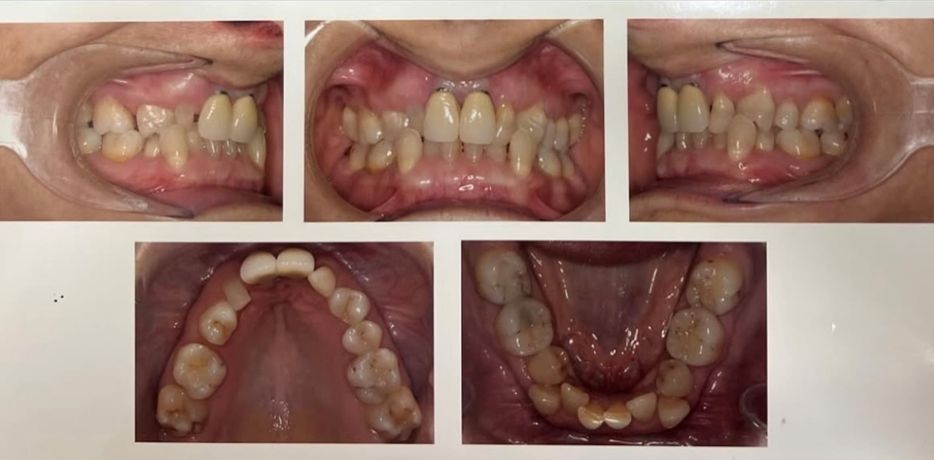

Caso 3

La paciente de este caso lleva implantes en 24 25.

El sector anteroinferior presenta apiñamiento, y sus dientes en general, torques muy negativos.

El tratamiento elegido ha sido ortodoncia invisible, con la cual expandiremos las arcadas corrigiendo las inclinaciones de sus piezas y el apiñamiento mencionado, sin necesidad de retirar los implantes que lleva.